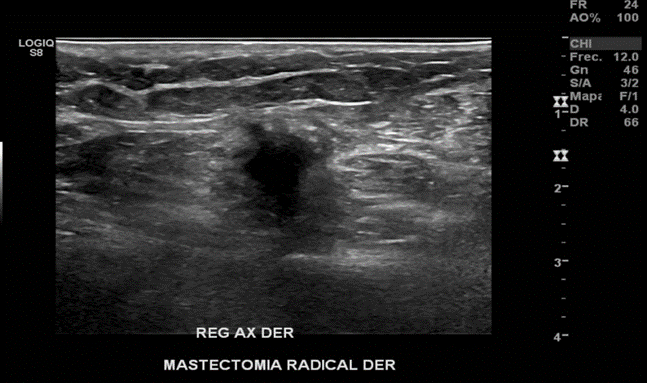

Nódulo sólido, hipoecogénico, de bordes irregulares, más alto que ancho, con sombra acústica posterior y con señal al Doppler a 12cm de cicatriz en región mamaria derecha hacia región axilar del mismo lado. Probable recidiva.

En región axilar derecha se observa imagen nodular, hipoecoica, de bordes mal definidos, de 16x12 mm.